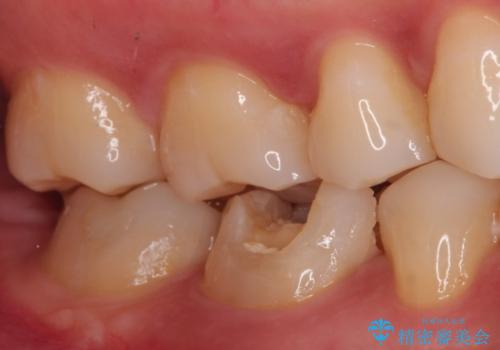

- 奥歯の治療の継続を主訴に来院された患者様です。

他院にて根管治療を行ったそうですが、ラバーダムを使用していなかったため、クラウン修復の前に当院の治療を希望され受診されました。

根管内に充填されている材料は、スカスカの状態で簡単に除去ができました。